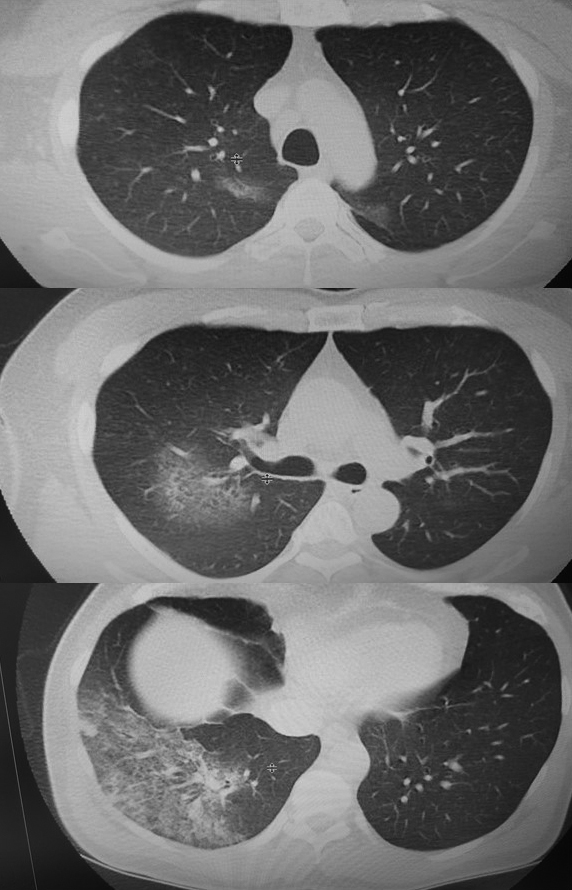

49 yaşında erkek hasta 4 gündür devam eden halsizlik, iştahsızlık, tat-koku alamama yakınmalarıyla başvurdu; ateş ve baş ağrısı yakınması yoktu. Hastanın toraks BT’sinde daha çok sağ alt lobu tutan, her iki üst lobda posterior segmentlerde, majör fissür önüne düşen alanlarda da izlenen buzlu cam görüntüleri izlendi (Resim 1). Periferik kan incelemesinde; lökosit 13 200/mm3 (11 800 nötrofil, 900 lenfosit), biyokimyasal analizlerde ALT 50 (Referans değer-RD: 5-41 Ü/lt), LDH 282 (RD: 135-225 Ü/lt), GGT 91 (RD: 8-61), sodyum 131 (RD: 135-145 mEq/lt), klor 95 (RD: 98-107 mEq/lt), fosfor 2.3 (RD: 2.6-4.5 mEq/lt), total protein 6.38 (RD: 6.6-8.7 gr/dl), CRP 258 (RD: 0-5 mg/dl), D-dimer 385 (RD: 0-243 ng/ml), ferritin 540 (RD: 30-400) idi. Diğer periferik kan ve biyokimyasal testler normaldi. Radyolojik olarak pnömoni düşünülen olguda rutin idrarda legionella antijeni istendi. Hastaya ampirik hidroksiklorokin ve favipiravir başlandı. Ertesi gün parmak ucundan ölçülen satürasyon değerleri,10 litre rezervuarlı nazal oksijen ile 80 seviyelerine düşünce hasta yoğun bakıma alındı. Tedaviye imipenem eklendi. İdrarda Legionella antijeni pozitif saptanan hastaya klaritromisin başlandı. Sodyum değerleri 108 mEq/lt’ye kadar düştü ve bilinç kaybı nedeniyle entübasyona gidildi. Sodyum replasmanı ve antiepileptik tedavi başlanan hastada epileptik eşiği düşürebileceğinden imipenem tedaviden çıkarıldı. COVID-19 PCR sonucu iki kez negatif çıktı. Ekstübe olan ve radyolojik düzelme gözlenen hasta önerilerle taburcu edildi. Bu olgu tat ve koku alamama yakınmasının COVID-19 dışı mikroorganizmalarda da olabileceğini; multilober ve posterior tutuluş gösteren buzlu cam görüntülerinin COVID-19’a spesifik olmayıp Legionella infeksiyonunda da görülebileceğini bize gösterdi.